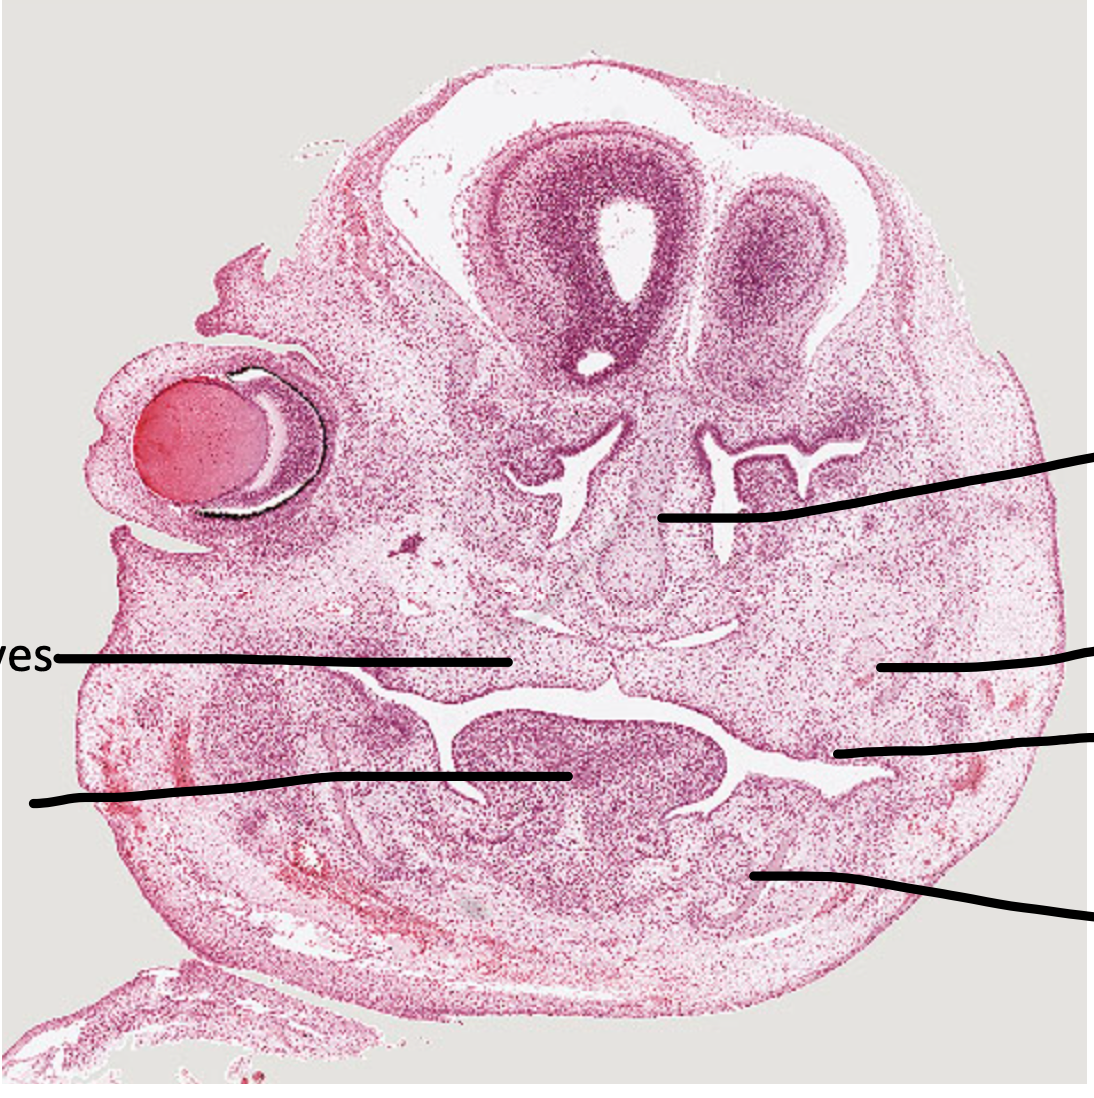

3

Q

A

developing tooth -> dental lamina and tooth germ

4

meckel’s cartilage

5

tongue

9

dental lamina

18

early tooth development